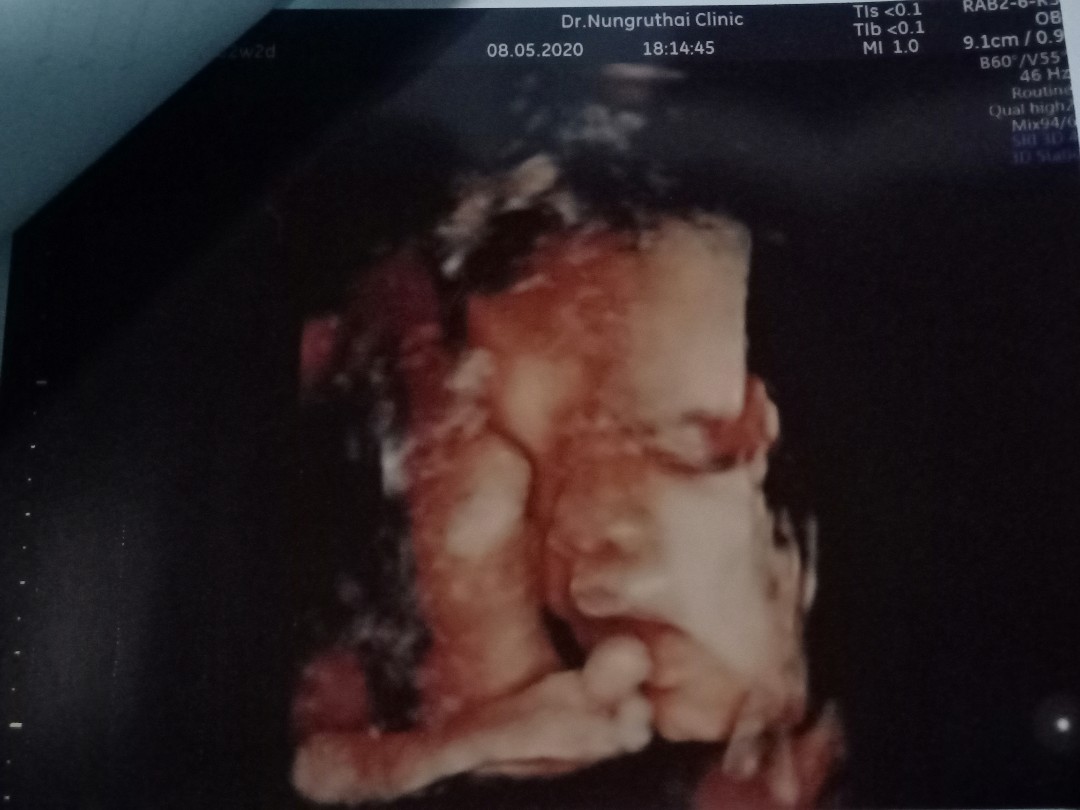

31 สัปดาห์ค้า. นอนยิ้มชูนิ้วโป้งเลยค้า